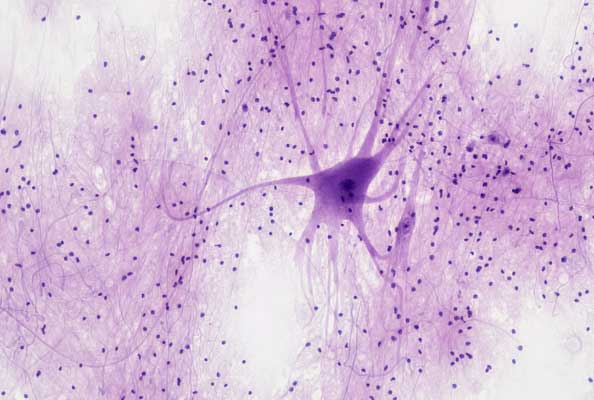

GBM(胶质母细胞瘤)是一种中枢神经系统恶性肿瘤,常见于大脑半球,是恶性程度最高的原发性脑肿瘤,占所有胶质瘤的50%以上,具有侵袭性强、进展快、预后差、复发率高的特点。而GBM内存在高表达CXCR4的GSCs(GBM干细胞)则是该肿瘤具有这些特点的罪魁祸首,它不仅促进肿瘤进展、转移及放疗抵抗,还能顺着CXCR4/CXCL12信号通路迁移到健康脑区使得病灶转移,为肿瘤复发埋下种子。除却以上特性,GSCs还会分泌免疫抑制因子使得肿瘤微环境形成“免疫荒漠”,而传统免疫制剂难以穿透血脑屏障,且不足以精准靶向GSCs达成免疫激活的作用。